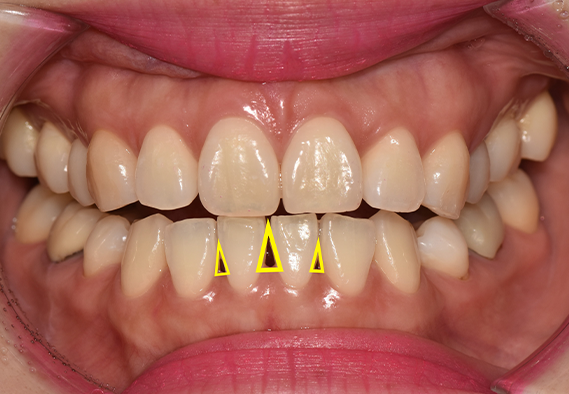

치아 사이사이에 존재하는 빈 공간,

치과 용어로는 흔히 ‘블랙 트라이앵글’이라고 부르는 현상에 대한 것입니다.

실제 환자분들 입장에서의 블랙 트라이앵글 현상은

심미적으로 보기 좋지 않다는 이유에서 고민이 되는 일이 많은데요.

가장 첫 번째로, 블랙 트라이앵글 현상이 이미 보이는 치아라면

우선적으로 심미적인 문제가 대두될 수 있는데요.

치아 사이사이 잇몸으로 채워지지 못한 여러 빈 공간은

흔히 노안이나 불균형한 인상을 심을 수 있어,

대외적으로 다양한 불편함을 느끼게 됩니다.